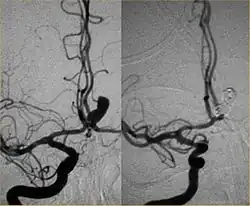

Parallel to the development of catheters, in the radiology and neuroradiology units, image technology dramatically improved: Charles Mistretta in 1979 invented digital subtraction angiography (DSA), the technique currently in use. It consists of performing skull radiography under basic conditions which are then "subtracted" to the image after contrast media injection, to provide an image where only brain vessels are displayed, with great improvement in the diagnostic potential.

Cerebral angiography was developed by Portuguese neurologist Egas Moniz at the University of Lisbon, in order to identify central nervous system diseases such as tumors or arteriovenous malformations. He performed the first brain angiography in Lisbon in 1927[3] by injecting an iodinated contrast medium into the internal carotid artery and using the X-rays discovered 30 years earlier by Roentgen in order to visualize the cerebral vessels. In pre-CT and pre-MRI, it was the only tool to observe the structures within the skull and was also used to diagnose extravascular pathologies.